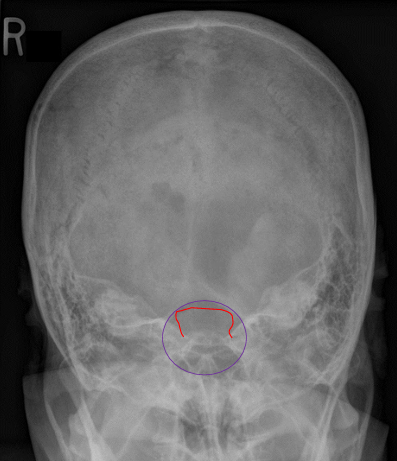

Critique - LAT Skull

F/E: manibular rami SI anterior arch of C1

excessive: posterior cranium SI on the posterior arch of C1

Tilt: separation of the orbital roofs inf/sup (sharper vs. duller)

Rotation: ant/post SI of EAM, mandibular rami, greater wings, cranial cortices